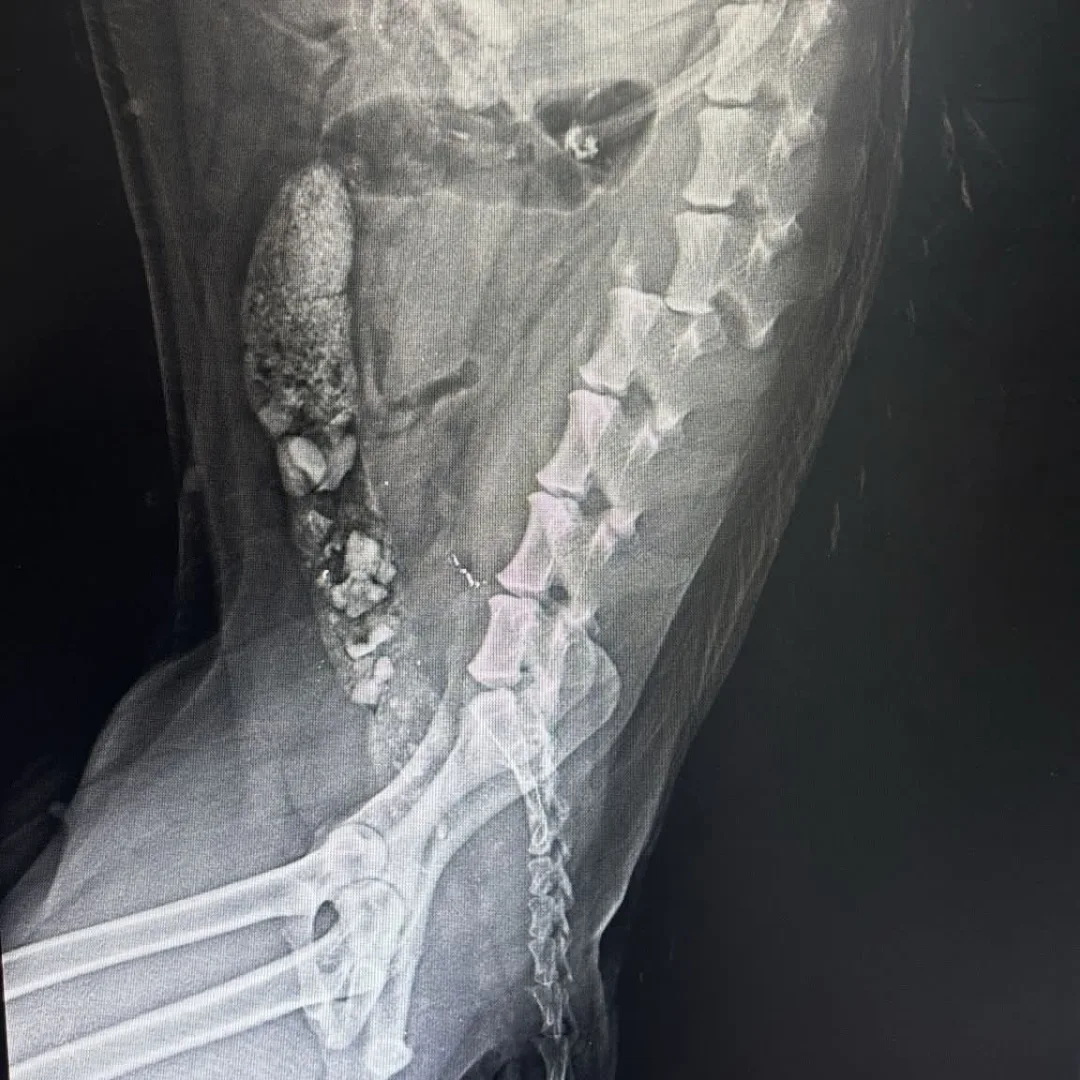

- #AMAPOLA: Atropellada el viernes con fractura de columna. Era cogerla o eutanasia, y bueno, pues aquí está. Con tratamiento y en reposo hasta rehabilitación y silla.